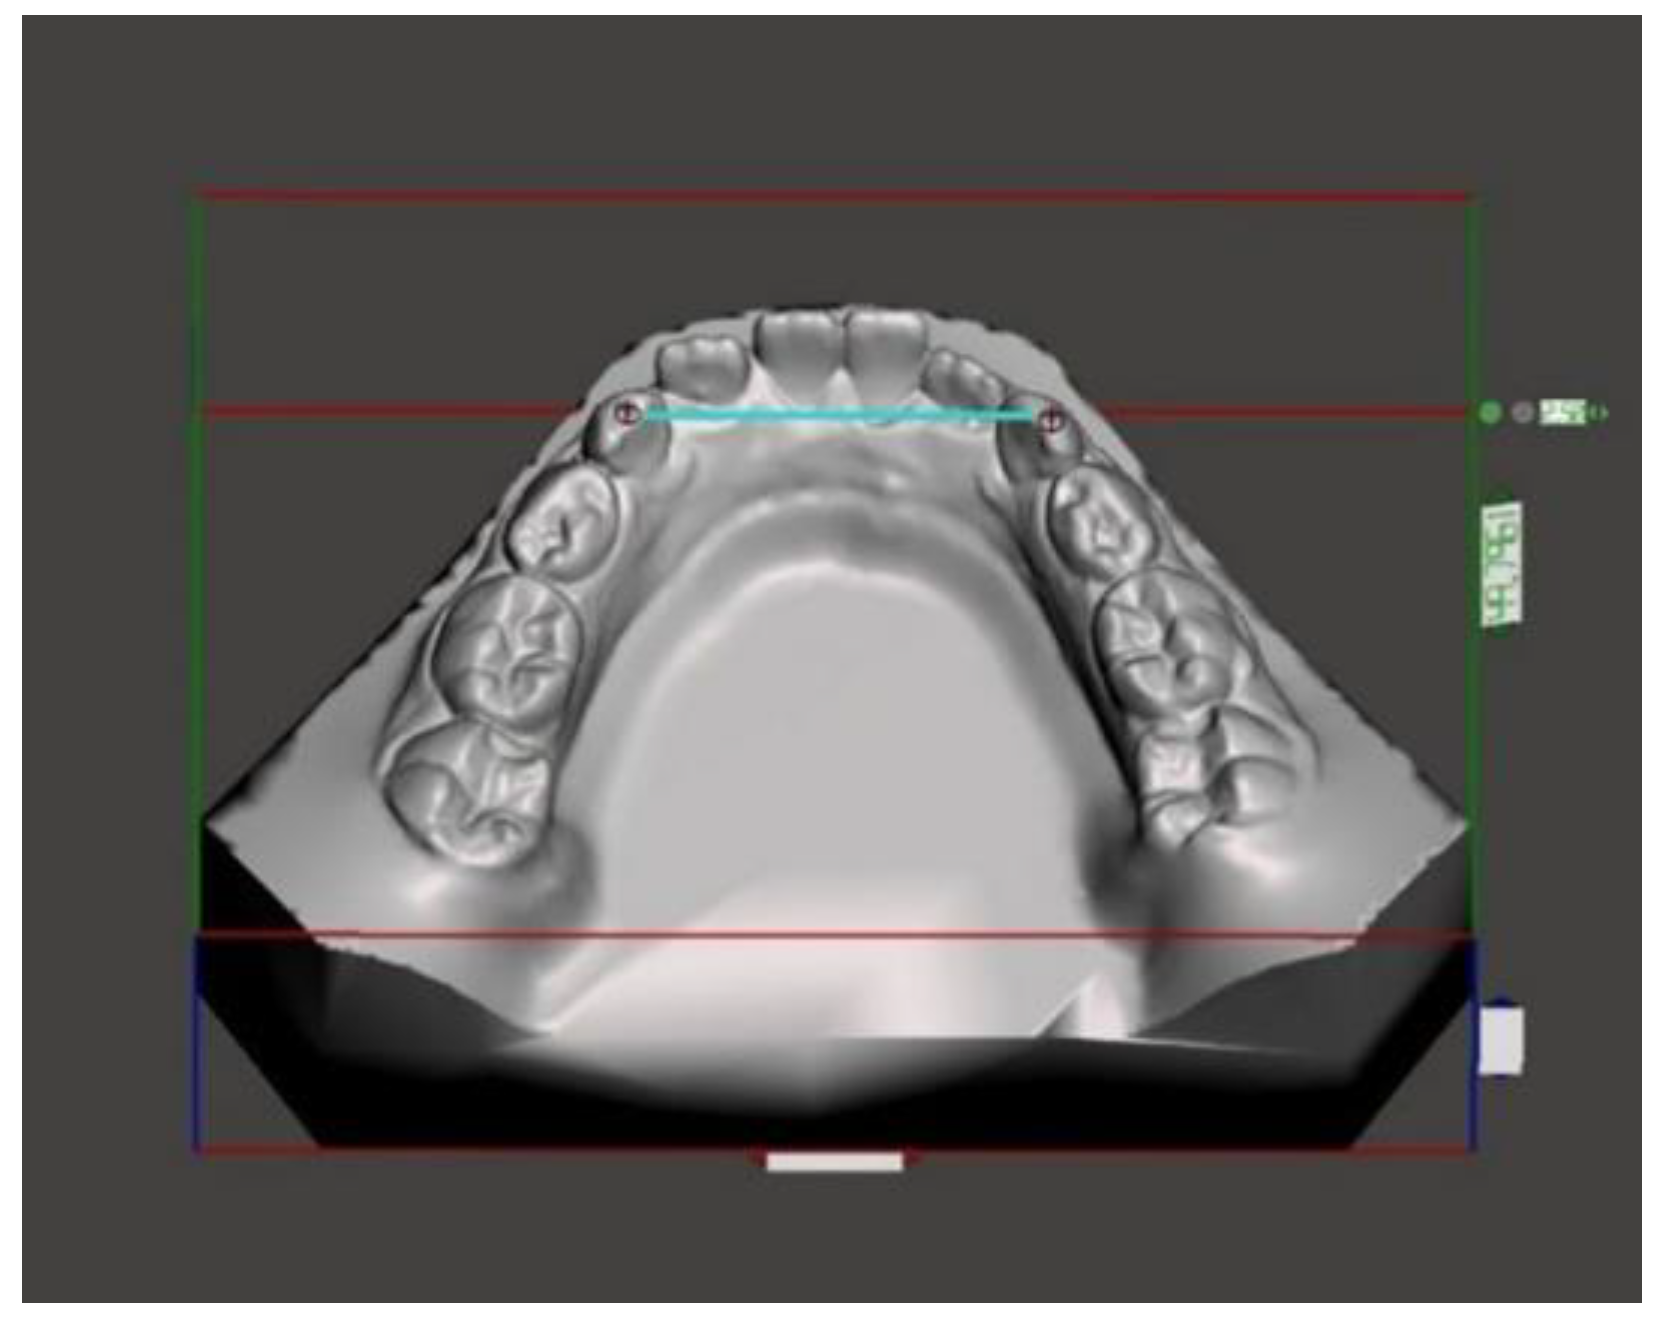

Figure 2.

Anterior mandibular width.

Figure 3.

Posterior mandibular width.